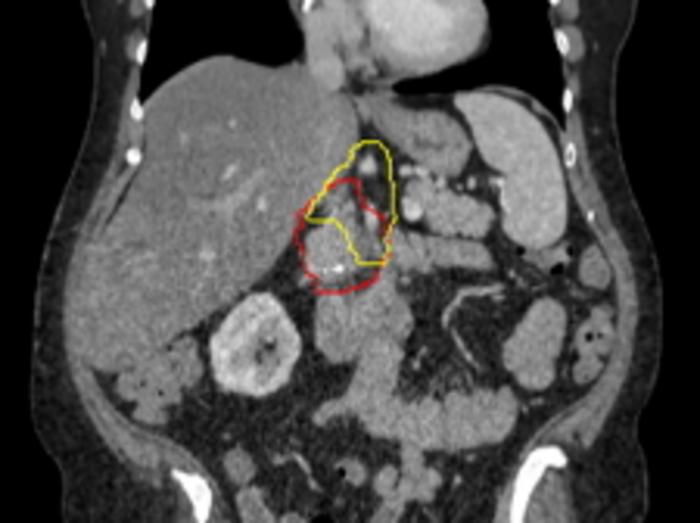

Image of a what is targeted with radiation. Red represents the pancreatic tumor, which is contacting with a major nearby artery. Yellow represents the Baltimore Triangle, which is now targeted in all patients, in addition to red volume. (IMAGE)

Image of a what is targeted with radiation. Red represents the pancreatic tumor, which is contacting with a major nearby artery. Yellow represents the Baltimore Triangle, which is now targeted in all patients, in addition to red volume.